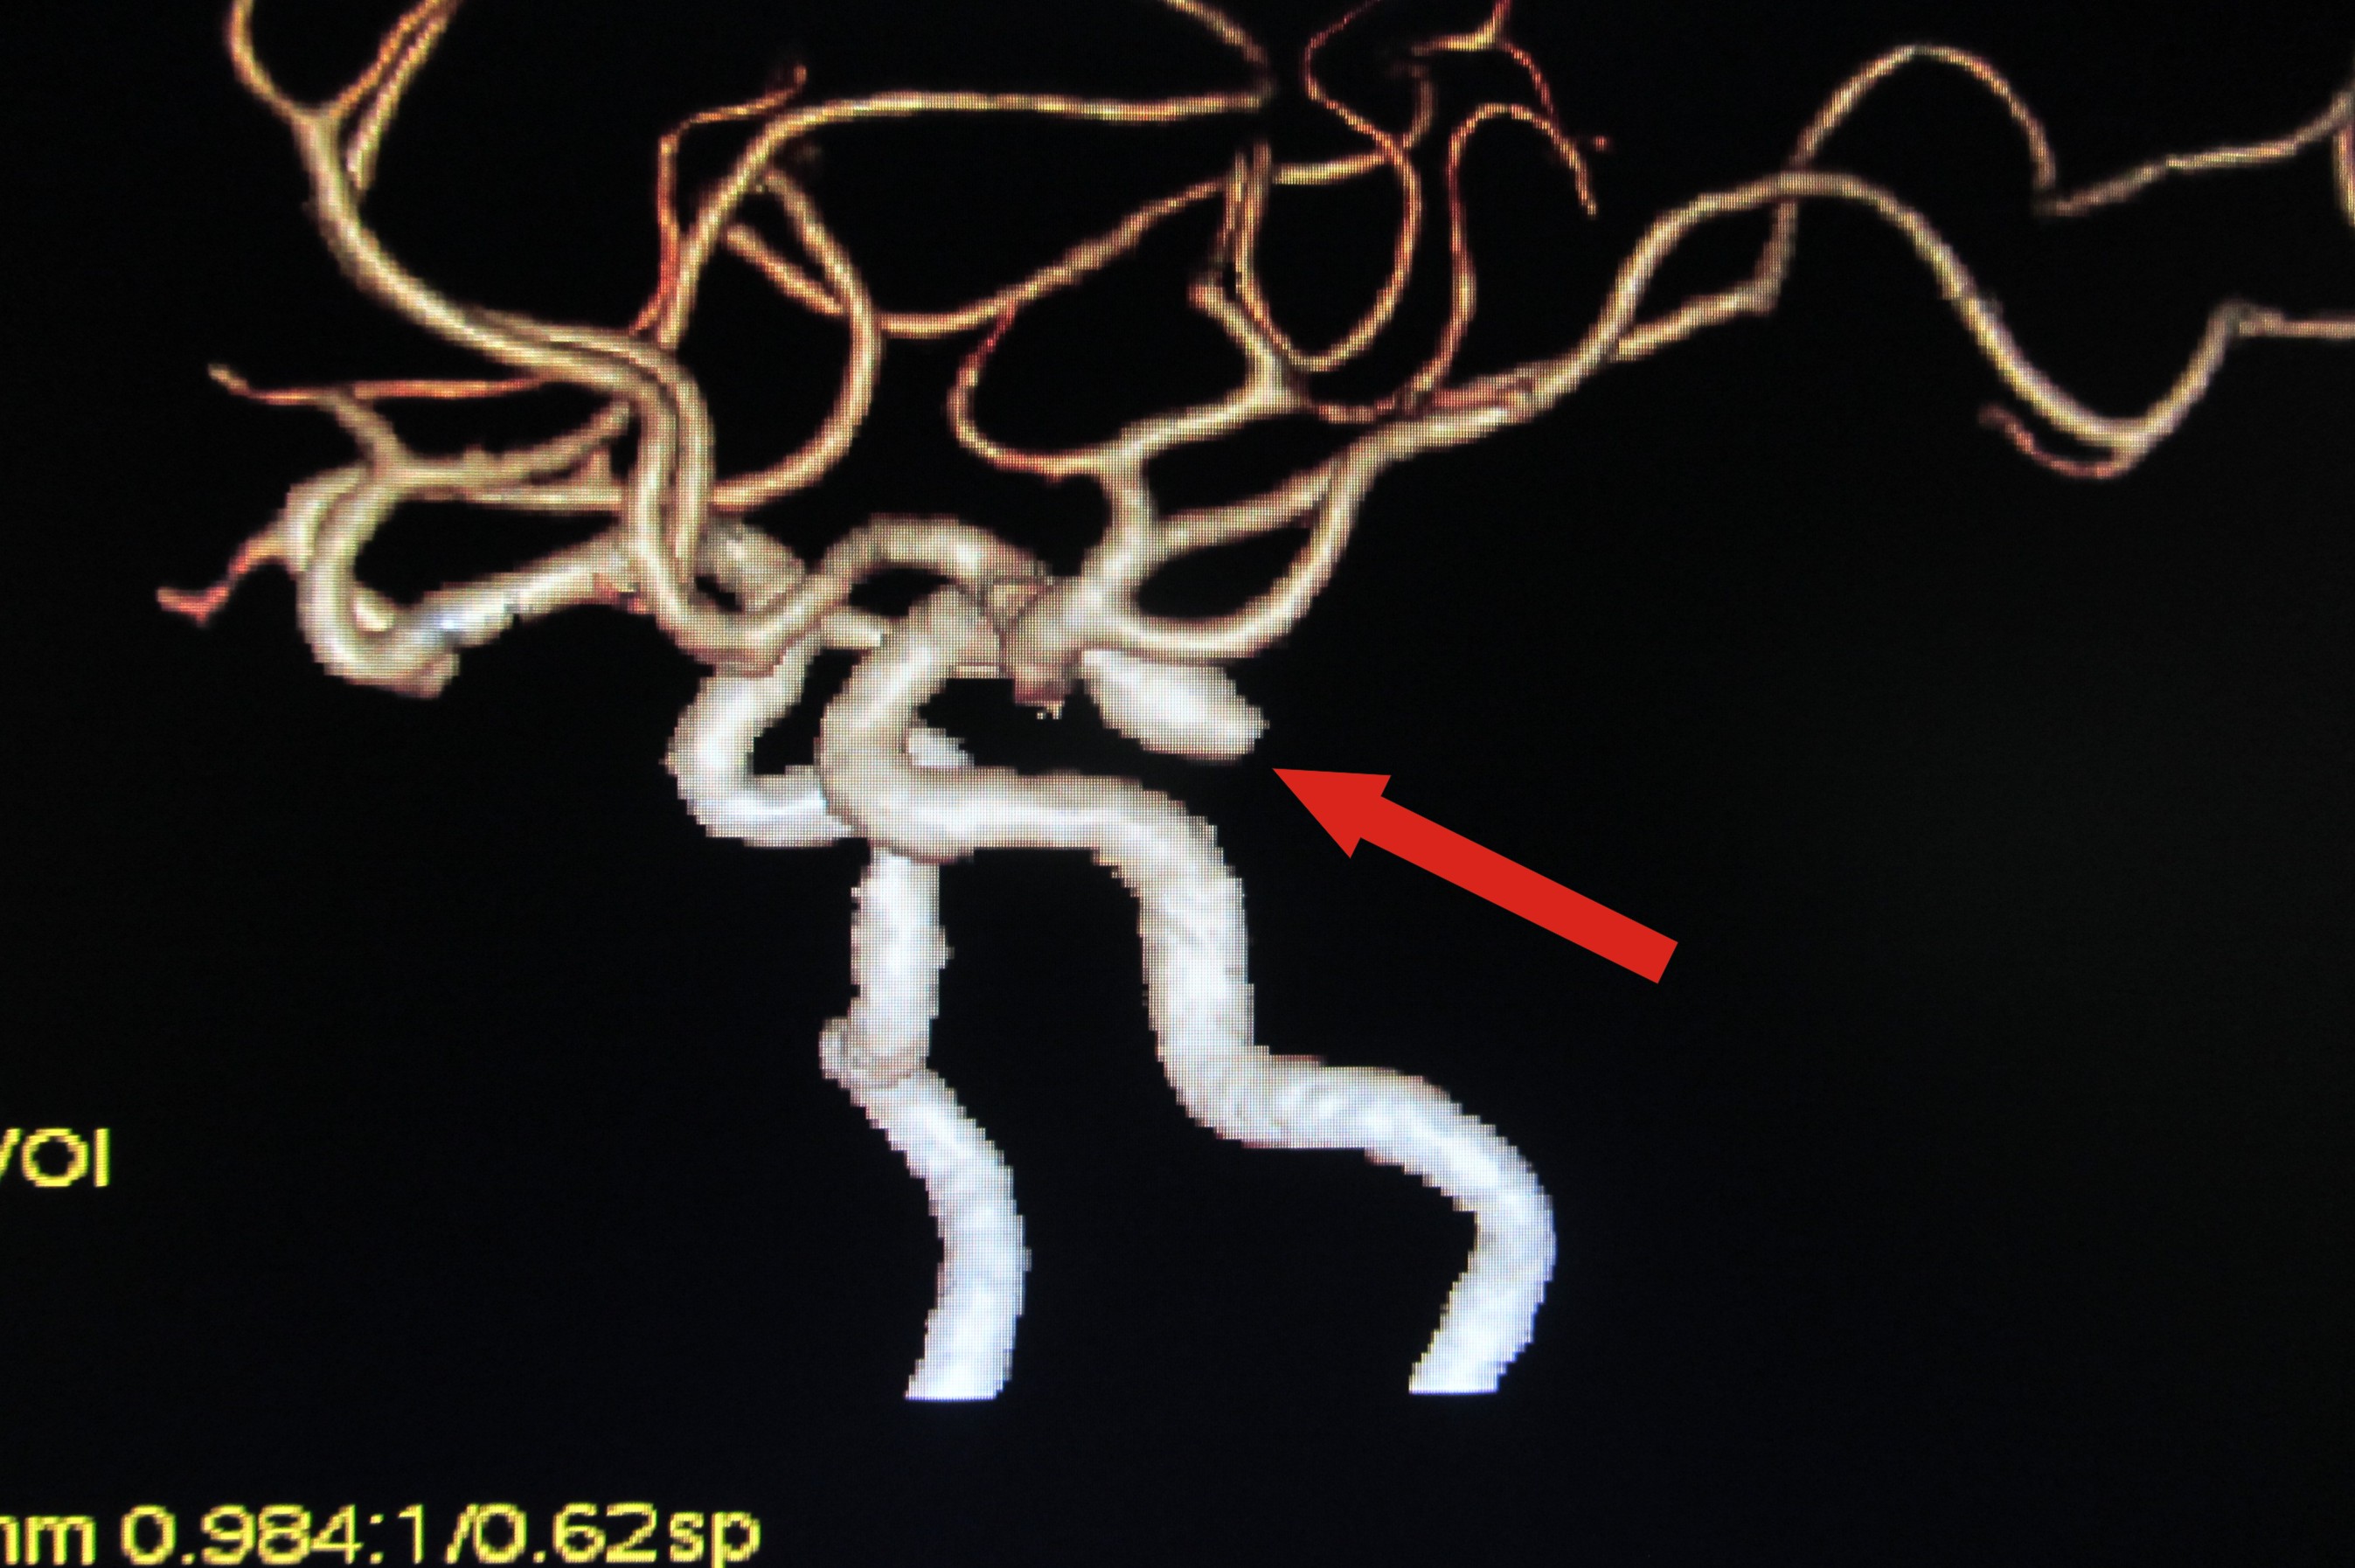

神经外科安排病人进行一种特殊的检查:颅脑CTA,这是我院新购进128层高级螺旋CT开展的新项目。检查结果发现,患者颅内存在一个巨大的“动脉瘤”(左侧后交通动脉瘤)。科室讨论一致认为,患者多年眼疾的“肇事者”就是这个颅内动脉瘤。随后,神经外科为患者进行了微创血管内介入治疗。手术后眼疾症状逐渐得到改善,困惑病人多年的眼疾终于得到治愈。

CTA发现巨大颅内动脉瘤(箭头所示)